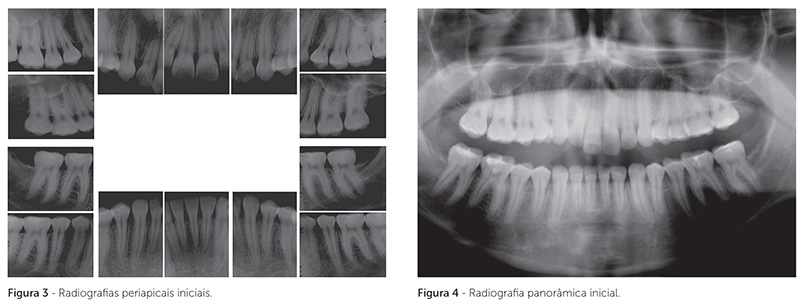

O exame intrabucal revelou a presença de má oclusão de Classe II, 1ª divisão de Angle, arcadas dentárias superior e inferior expandidas e assimétricas, sobressaliência de 6mm, mordida aberta posterior, com contato oclusal apenas nos segundos molares, e desgastes excessivos nas cúspides dos molares superiores e inferiores, devido a uma tentativa de ajuste oclusal (Fig. 1, 2). Os incisivos superiores e inferiores estavam protruídos e inclinados para vestibular, com arredondamento apical das raízes dos incisivos superiores (Fig. 3, 4, 5).

Foi obtido bom paralelismo radicular ao final do tratamento, conforme observado na radiografia panorâmica (Fig. 9). As radiografias periapicais mostraram leve aumento no remodelamento apical dos incisivos (Fig. 10).